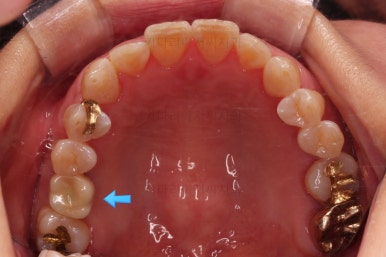

초진 때의 사진입니다.

전반적으로 치열이 삐뚤하고 불균일한 양상이긴 하지만 꼭 이런 부분들까지 교정을 해야 하는 건 아니에요.

제일 하단의 X-ray에서 문제점이 보이는데요.

해당 부분의 어금니가 1개가 없었어요.

어금니가 없어진지 꽤 시간이 흘렀기 때문에 몇 가지 문제점이 나타나는데요.